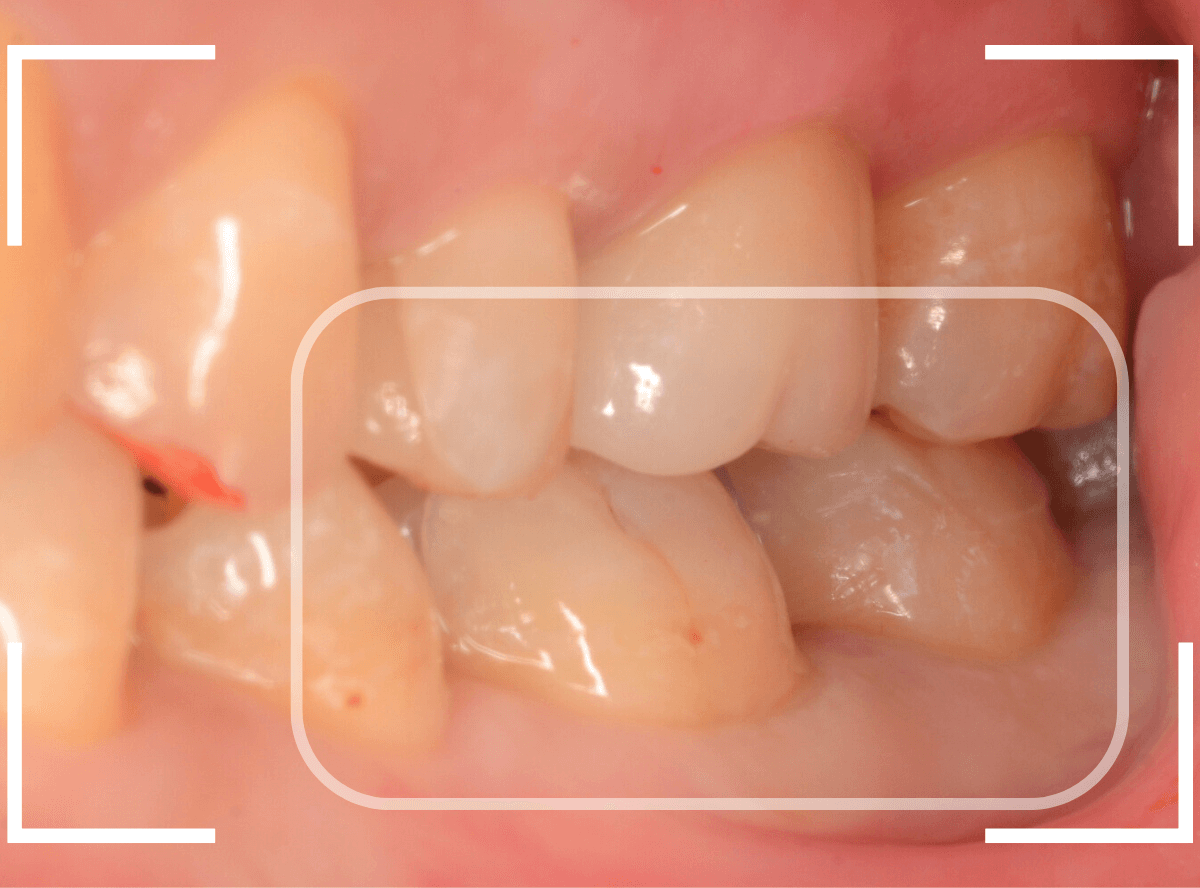

「下の奥歯の銀歯を白くしたい」というご希望の患者さんです。

メタル・インレーとメタル・クラウンが入っていますね。

検査の結果、再製に問題なさそうでしたので、治療を進める事になりました。